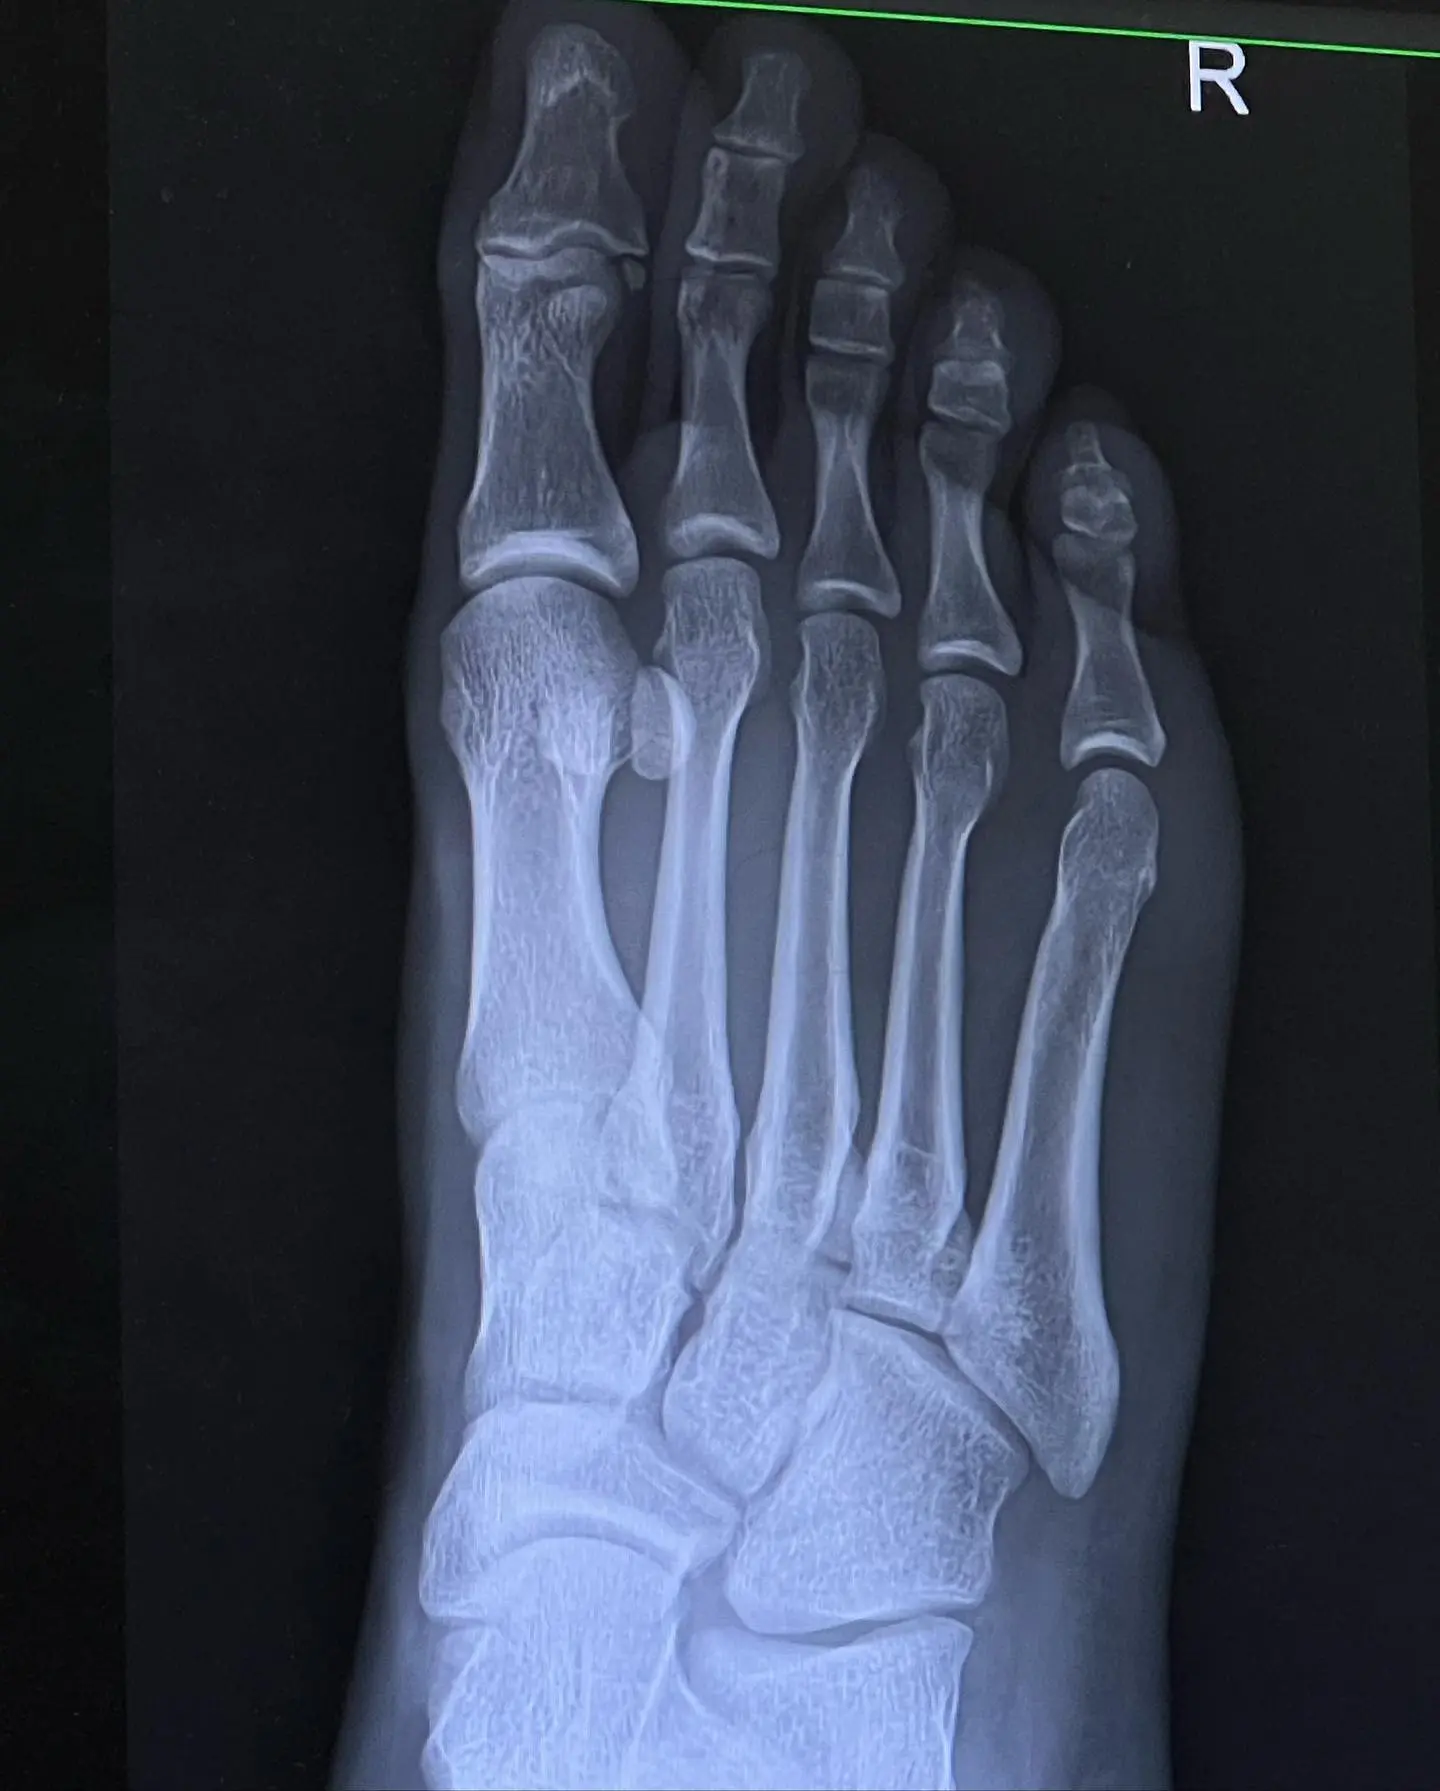

ด้าน ดีเจบอส ณัชพงศ์พล ได้ออกมาโพสต์ภาพ พร้อมเล่าเหตุการณ์ผ่านทางอินสตาแกรมส่วนตัวว่า “เรียบร้อย!! 2-1 🔴 เอ๊ย ผิดครับ!!! เหล็กทับ 👣 เต็มๆ เหล็ก 11 โล (เหล็กล้วนไม่มียางผสม) หลน จากระดับ หัวไหล่ เหลี่ยมลง เท้า เต็มๆจากทรง คือ ดูไงไม่น่ารอด กระดูกน่าจะไม่หัก ก็ ต้อง ร้าว สรุป!! เอ็กซเรย์ ออกมา หมอ บอกเกิ๊นน ไม่เป็นอะไรเลย กระดูกปกติแข็งแรงมาก เอ็นไม่ขาด กล้ามเนื้อไม่ฉีกขาด #ขาผมอดาแมนเที่ยม 🦿เตือนทุกคนนะครับ ใส่รองเท้าทุกครั้งเวลาออกกำลังกายอะไรที่อันตราย หนักจะได้เบาลง ถ้าไม่มีรองเท้าถุงเท้า ผมว่าน่าจะหักละเอียดเลย GYM ไม่ใช่ของเล่นนะครับ 🦾🦿🧠 #เหมือนปีนี้มีแต่เรื่องซวยดีสุดในชีวิตมีแค่เรื่องเดียว” ซึ่งเพื่อนคนบันเทิงหลังจากที่ดีเจบอสโพสต์ไปก็เข้ามาส่งกำลังใจให้อย่างเนืองแน่น